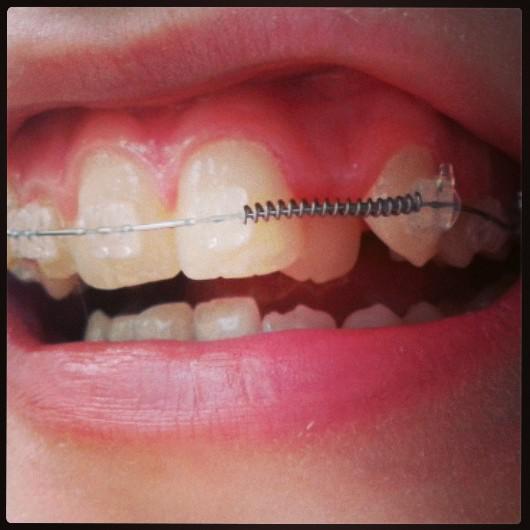

1380563758586.jpg

>>55610461

Есче

Аноним Пнд 30 Сен 2013 21:56:18  #48 №55610573

1380563778882.jpg

Такая поебень, в общем.